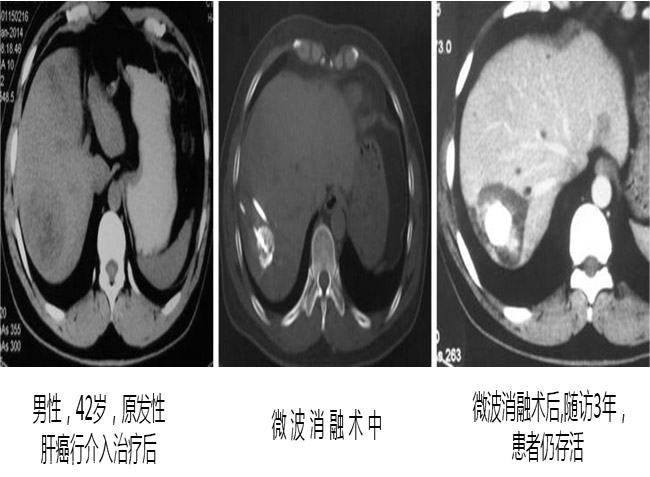

成功案例CT影像对比:

案例二: